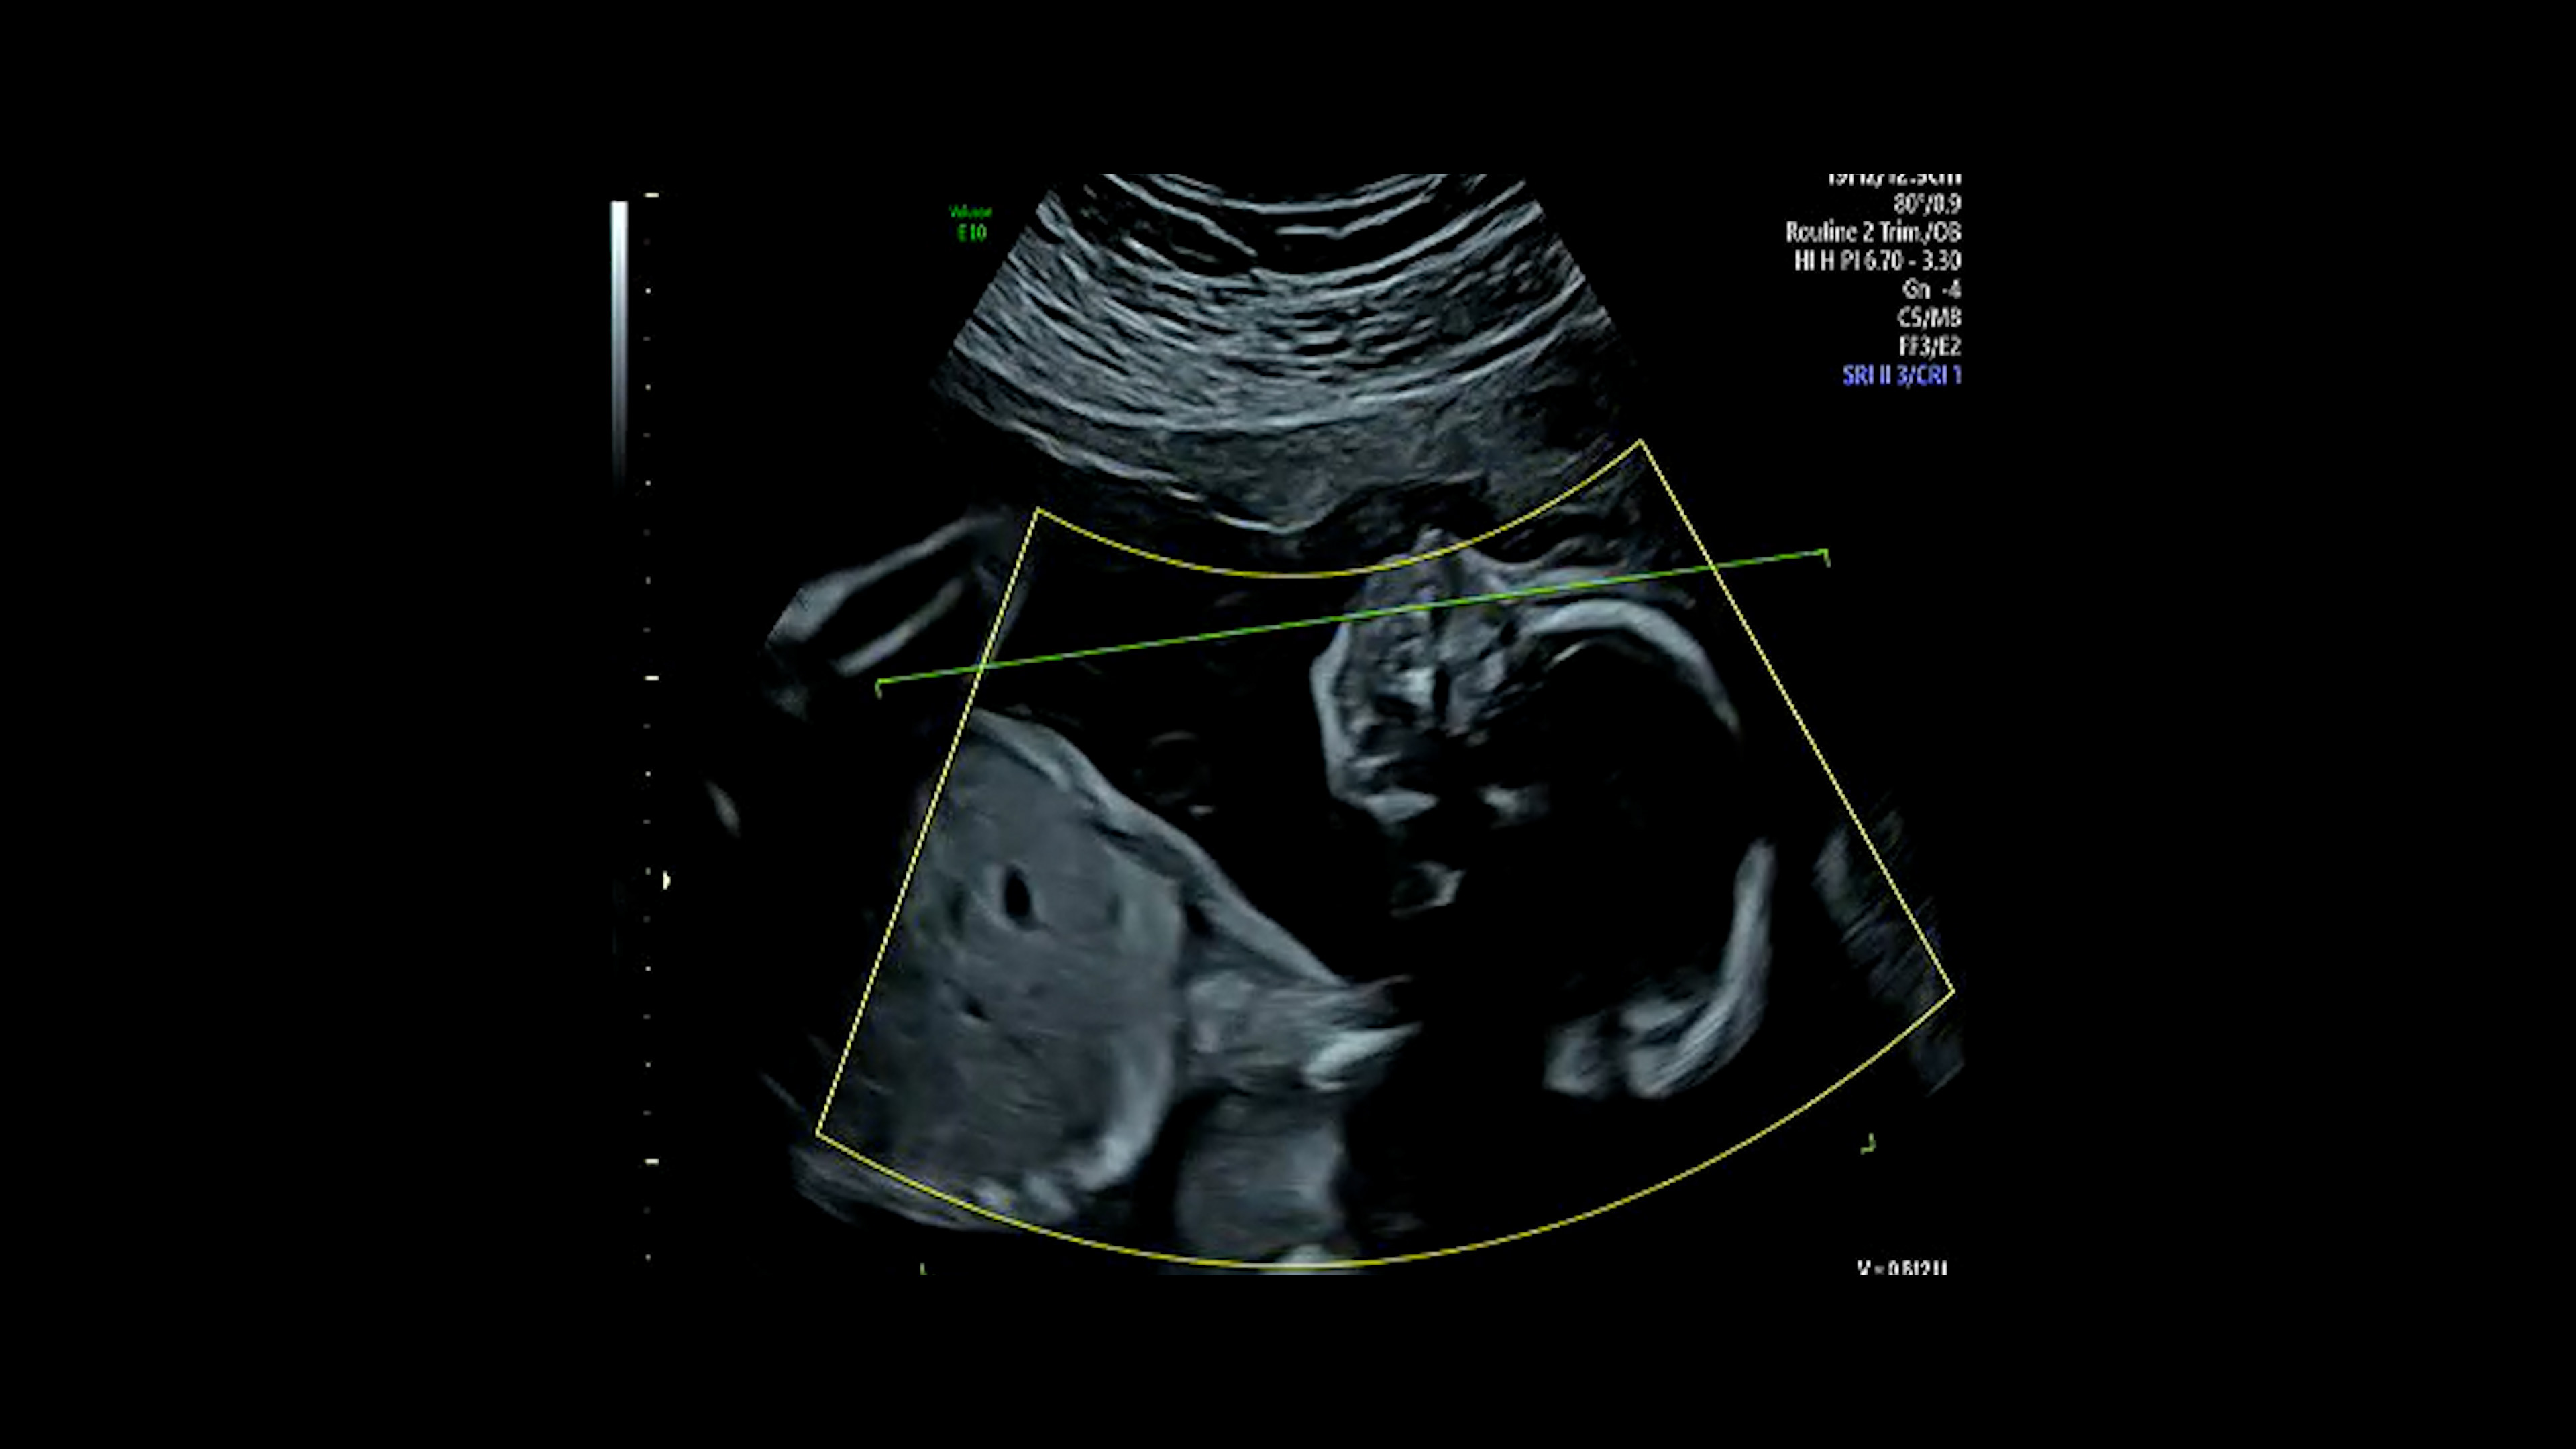

A Place Like This is an intimate documentary by filmmaker Badoor Jbara, exploring love, identity, and belonging through her personal journey as a Palestinian citizen of Israel. The film traces her relationship with her husband Mustafa, their struggles to find a place in societies that label and exclude them, and the transformative moment of becoming parents during a time of war. Through pregnancy, political upheaval, and the decision to leave their homeland in search of a better future for their daughter, the film confronts questions of identity, alienation, and hope. Both deeply personal and universally resonant, it reflects the collective experience of Arab citizens in Israel—caught between cultures and longing for a place to truly belong.